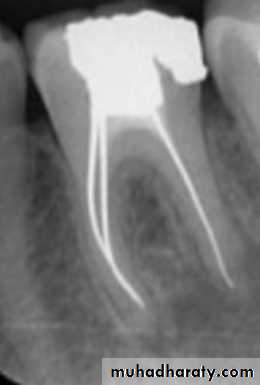

2- Gutta percha carrier devices: (Thermafil)

These are cores of metal or plastic coated with gutta percha. They are heated in an oven and then simply pushed into the root canal to the correct length. The core is then cut with a bur. A dense filling results, but apical control is poor and extrusions common. They are expensive and difficult to remove.Advances in gutta percha

A

B

C

D